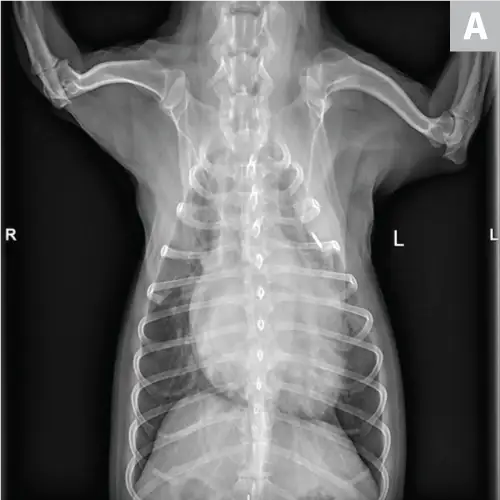

CDV should be suspected in poorly vaccinated dogs with multiorgan involvement. Dogs with CDV may have exhibited only respiratory signs before developing characteristic nonrespiratory signs.12 Radiographs may reveal a diffuse interstitial pattern (Figure 2). Diagnosis is supported by compatible clinical signs and complementary diagnostic testing (ie, real-time reverse transcription polymerase chain reaction [RT-PCR], serology, CSF pleocytosis). Conjunctival scraping and tissue-based immunohistochemistry may confirm diagnosis.

FIGURE 2

CDV pneumonia with a diffuse interstitial pattern confirmed by multisystemic signs, urine RT-PCR, and necropsy